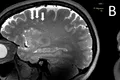

Un studiu fără precedent dezvăluie cum arată migrenele în creier